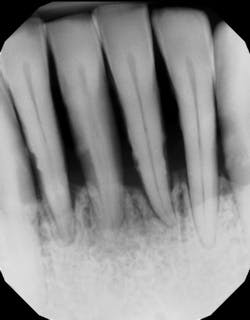

Pocket depth. Classic studies have shown that the deeper the periodontal pocket (the space between the gum and the tooth), the harder it is to remove the bacteria and calculus (tartar).2 For example, one study suggests that when probing depths are in the 1–3 mm range, removal of calculus during scaling and root planing can be 86% effective. That number drops to 32% when pockets are 6 mm or greater (figure 2).